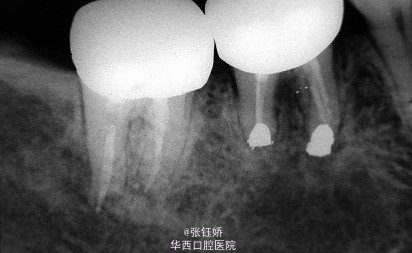

女,56岁,自觉左下磨牙区敏感不适,X线片示36牙已根充,远中根管超填,近中根管欠填,根管预备显示近中根管下段钙化,根尖周见较大暗影。考虑到患者牙合间距离很小不符合根尖手术适应症,故拟行意向性牙再植术。